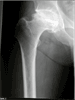

Post

Op

Total Hip replacement done via minimally invasive single incision

Progress

Patient with pain relief and good hip motion